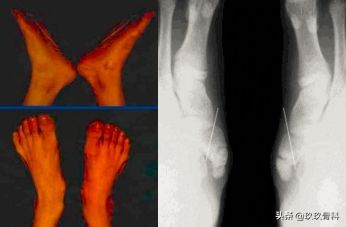

辅助检查

- X线 踝关节正侧位(必要时应加照踝穴位)

- B超

- MRI

应力位片